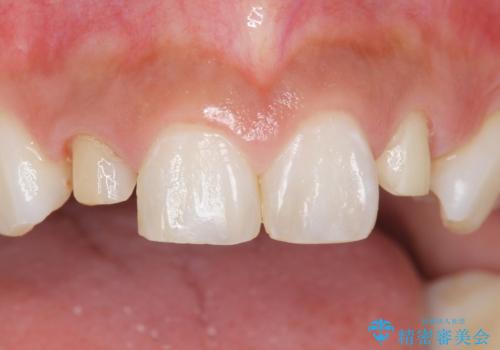

- 上の前歯の色と隙間を気にされ、来院された患者様です。

精査したところ、右上の側切歯(右上2)は神経が死んで変色しており、左上の側切歯と犬歯の間に2mm程度の隙間を認めました。

学生時代に舌側矯正をされており、通院が大変になり治療を途中でやめてしまったとのことでした。

矯正せずに早く治したいという強いご希望により、セラミッククラウンによる補綴治療(上顎両側2の2本)を行いました。